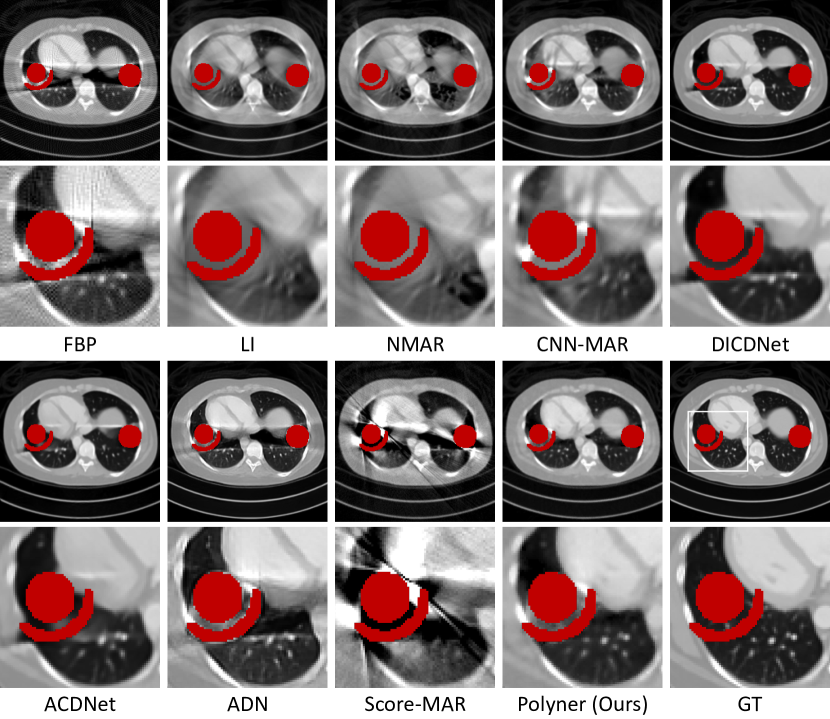

Refer to caption

Figure 2: Qualitative results of the compared methods on two samples (##\#124 and ##\#2) of the DeepLesion [43] and XCOM[44] datasets. The red regions denote metals.

Comparison on Simulation Data. Table 1 presents the quantitative results. On the DeepLesion dataset [43], ACDNet [13], our Polyner, and DICDNet [14] achieve the top three performances and significantly outperform other baseline models. Specifically, our Polyner produces the second-best performance, trailing slightly behind ACDNet [13] by only -0.62 dB in PSNR. However, on the XCOM dataset [44], we observe that DICDNet and ACDNet trained on the DeepLesion dataset [43] suffer from severe performance drops due to the OOD problem. Their performance is even lower than that of the model-based NMAR [11] algorithm, with -3.98 dB and -3.59 dB in PSNR, respectively. In contrast, our Polyner obtains the best performance, slightly outperforming CNN-MAR trained on the XCOM dataset [44] by +0.22 dB in PSNR. Fig. 2 shows the qualitative results. Notably, three model-based algorithms (FBP [3], LI [10], and NMAR [11]) and two unsupervised methods (ADN [30] and Score-MAR [9]) cannot yield satisfactory results, exhibiting severe artifacts on both datasets. Conversely, while DICDNet [14] and ACDNet for the DeepLesion dataset [43] yield excellent MAR performances, their results on the XCOM dataset [44] include severe artifacts. This contrasts with CNN-MAR [7], which achieves superior results for the XCOM dataset [44] but not for the DeepLesion dataset [43]. These visual inspections are consistent with the above quantitative comparisons. Remarkably, our proposed Polyner presents clean and fine-detail CT reconstructions for both datasets, indicating its robustness and superiority over existing MAR methods. More visual results can be found in the supplementary material.